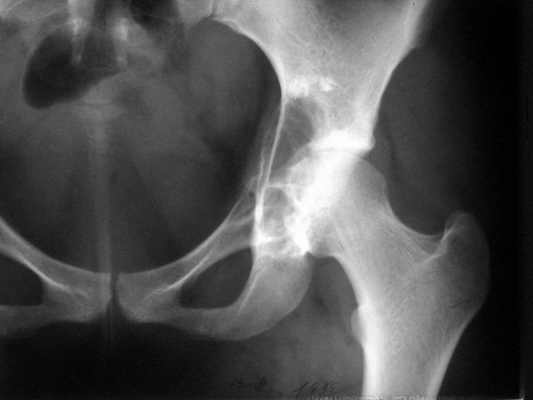

Остеобластокластома вертлужной впадины

Женщина 22 лет поступила с протрузией вертлужной впадины.Рентгенограммы (1, 2) с интервалом в 1 год. В онкодиспансере сделали биопсию - ОБК без малигнизации. Какой объем операции здесь следует предпринять? Есть ли какие-то шансы на первичное эндопротезирование? Где такие операции делают? В том числе в Европе. Заранее спасибо.

The xray appearance is consistent with a bengin aggessive or malignant lesion involving both the acetablum and the femoral epiphysis (there appears to be erosions of the femoral head). The differential diagnosis would include non-tumor conditions such as Brown's tumor (a serum calcium should be measured), benign aggressive lesions such as GCT, ABC and chondroblastoma, and malignant lesions such as telangiectatic osteosarcoma and MFH of bone.

However, the extent of the tumor in the pelvis and lack of a cortical rim leading to a large uncontained defect would be too much bone loss for any type of acetabular reconstruction.

A wide resection with reconstruction with a saddle modular prosthesis would be an option depending on the status of the remainder of the ilium.

looking to the X-rays and CT scan it appears this young lady has an aggressive bone leasion.

The X-ray and CT scan appearance is likely as the chondrosarcoma what is seldom but common

finding in the replacement surgery of the hip. Having precise histological, CT and MRI data should be planed the amount of surgery after detailed discussion with patient. There is no any possibility to perform primary replacement. If there is the chondrosarcoma hemipelvectomy would be the most live saving procedure. If there is an aggressive giant cell tumor or other findings about allografting, reconstructive surgery with custom made implant or saddle modular prostheses (W.Link) could be discussed. In other wards there are so many different thinks what should be discussed with patient